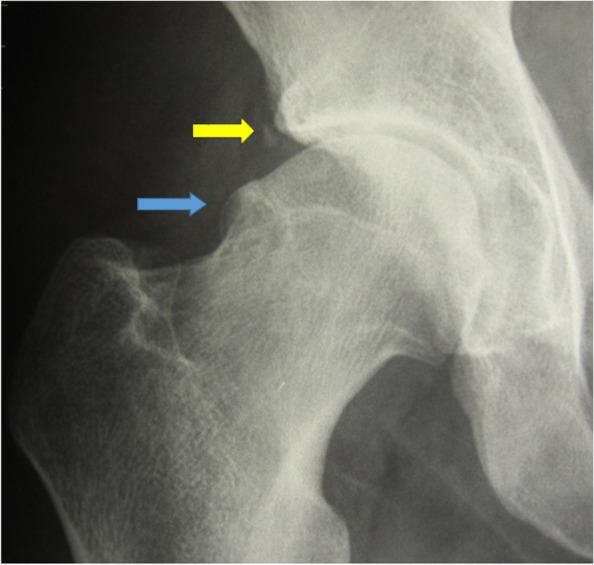

The femoral head-neck deformity associated with the Cam type of femoroacetabular impingement was observed in 61.6% of professional football players and only in 11.6% of the control group (p <0.01). The presence of "herniation pit" (11.6%) and os acetabuli (13.3%) also reached statistical significance in the professional football players group. In the other analyzed parameters, no statistically significant differences between the groups were observed.

White professional top-level football players have an increased incidence of abnormal lateral epiphyseal extension ("pistol grip deformity"), os acetabuli and herniation pits.